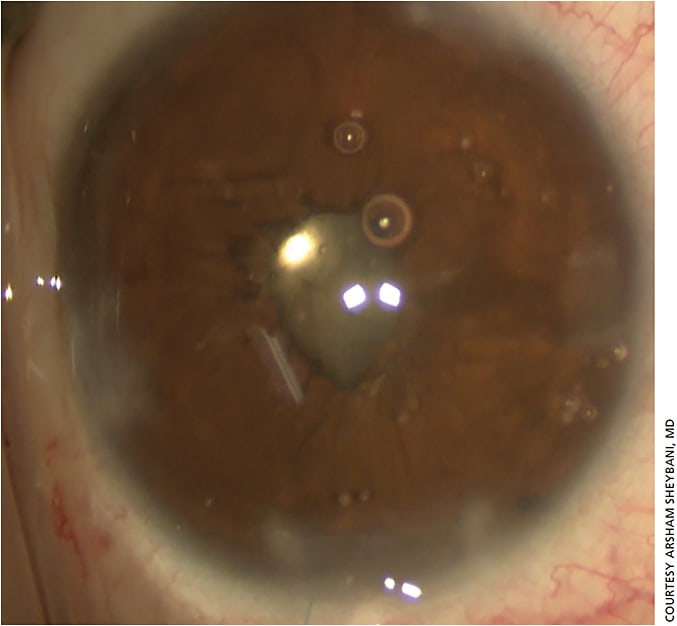

“For someone who’s just starting with the newer MIGS devices, the overarching piece of advice is to use whatever technology works best in your hands,” says Dr. Greenwood. “That’s what is going to be best for your patients, whether it’s the iStent (Glaukos) (Figure 1), the Hydrus (Ivantis) (Figure 2) or the Kahook Dual Blade (New World Medical).”

“The issue then becomes, how much tissue is there? If the iris was operated on before and the patient lost tissue, it’s a very different discussion,” Dr. Sheybani says (Figure 3).